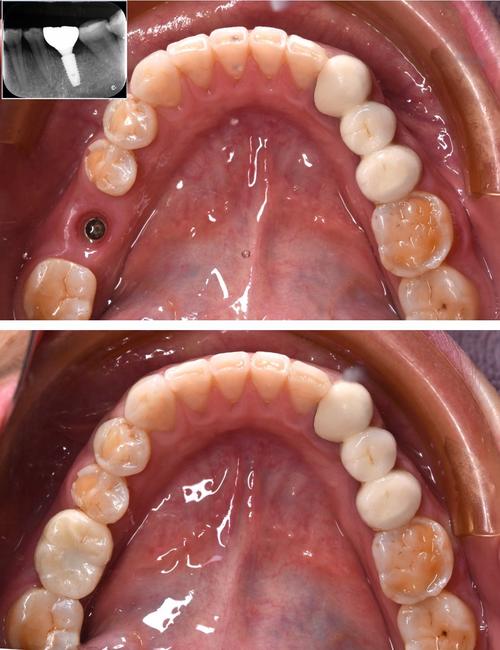

种植牙手术通常分为一期手术(植入种植体)、二期手术(安装基台)及牙冠修复三个阶段,具体流程如下:

- 缝合:将牙龈复位缝合,7-10天拆线,术后拍摄X光片确认种植体位置。

种植体植入后需等待骨结合完成,此期间需避免种植体受力,忌用患侧咀嚼,定期复查(术后1周、1个月、3个月),观察骨愈合情况,若骨结合良好(CBCT显示种植体周围骨密度增加、无透射影),可进入二期手术。

二期手术:安装基台(约30分钟)

- 暴露种植体:切开牙龈,去除种植体表面的愈合基台,暴露种植体内部连接结构。

- 安装基台:将愈合基台更换为永久基台(或暂时基台),基台作为种植体与牙冠的连接件,决定了牙冠的最终位置和咬合关系。

- 取模:用专用印模材料获取基台及牙龈形态,送技工所制作牙冠。

牙冠修复(约1-2周)

- 试戴牙冠:牙冠制作完成后(全瓷冠、烤瓷冠等),试戴调整形态、颜色、咬合,确保舒适无早接触。

- 粘接或螺丝固定:全瓷冠通常用树脂粘接固定,金属冠或螺丝固位冠可直接通过基台螺丝固定。

- 完成修复:最终调整咬合,术后告知患者注意事项,定期复查(每6个月1次)。